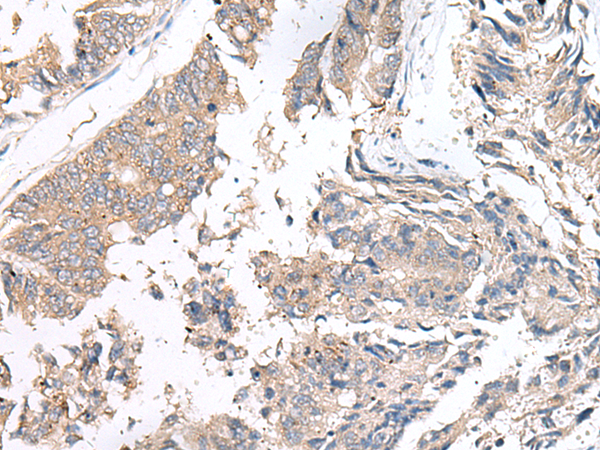

分类: 科研抗体货号: P10999别名: SWS; SJS2; STWS; CD118; LIF-R应用: IHC反应种属: Human